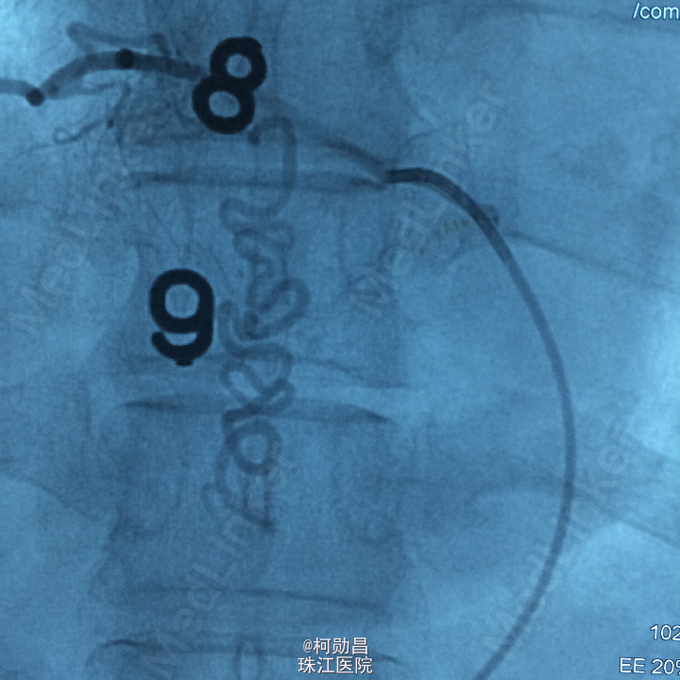

诊断:硬脊膜动静脉瘘 处理:予全麻下行栓塞治疗,选择予 withn-butyle-2-cyanoacrylate(医用胶)完全闭塞 。